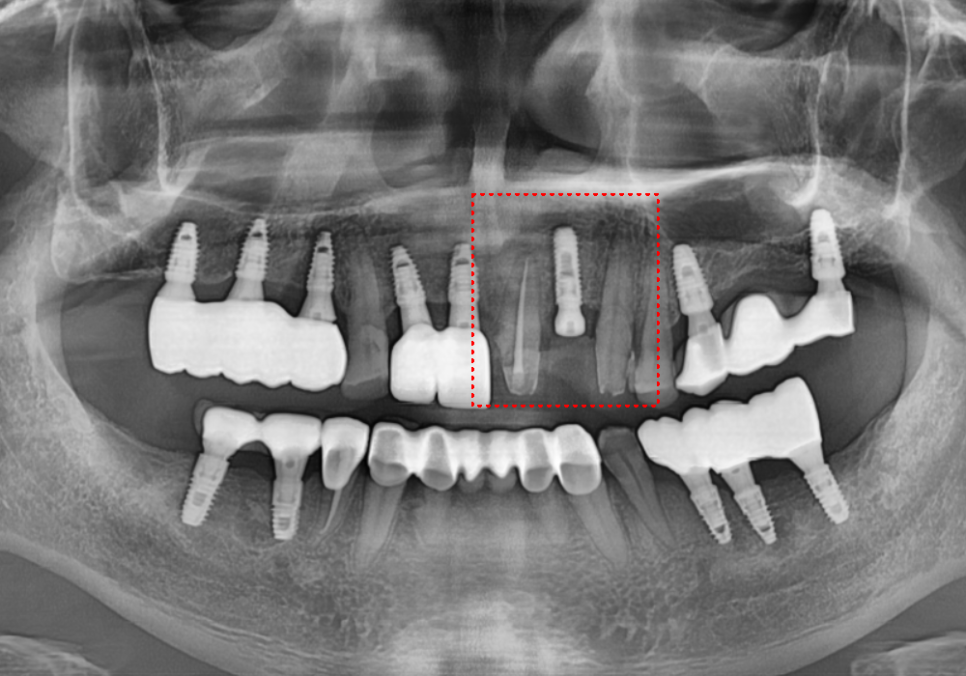

이 환자분은 오래전에

왼쪽 앞니부터 송곳니까지(#21~23)

치아 3개를 연결한

'브릿지' 치료를 받으셨다고 해요.

불편해하시는 부위를 자세히 살펴보니,

문제의 발단은

브릿지 끝 치아(#21)와

그 옆에 있는 임플란트(#11) 사이였습니다.

이 틈으로 계속 음식물이 꼈는데,

방치하다 보니 결국

심한 통증으로 이어진 것이죠.

엑스레이로 확인해 보니

역시나 예상이 맞았습니다.

230516

앞니 옆면을 타고 뿌리 깊숙이

충치가 까맣게 진행 중이었습니다.

원인은 바로

'제거되지 않은 음식물'이었는데요.

브릿지 틈새에 낀 음식물이

빠지지 않고 안에서 부패하면서,

보철물 속의 치아를

야금야금 녹이고 있었던 겁니다.